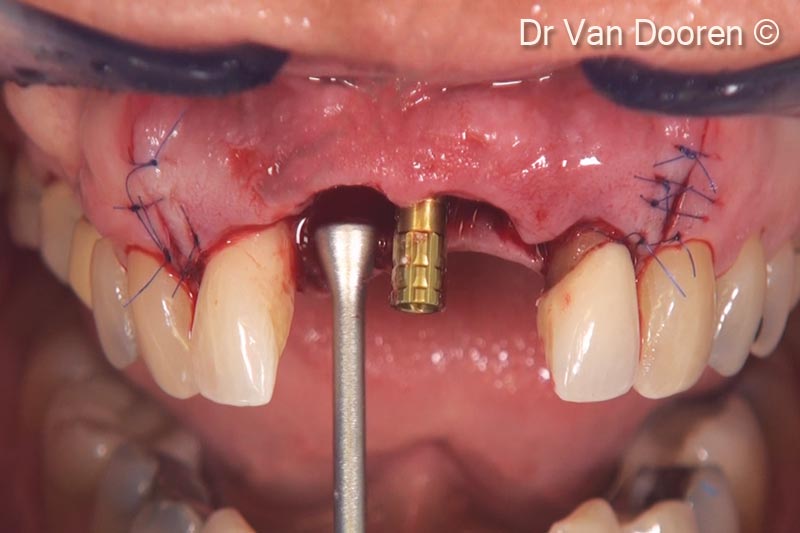

Đặt implant (V3/ RP 3,9 mm - 13 mm) bằng dụng cụ dẫn hướng MGuide (MIS). Vị trí vòm miệng để có được phục hình cố định bằng vít là điểm mấu chốt trong trường hợp cụ thể này

Sau khi đặt trụ tạm thời, OsteoBiol® GTO® được đặt và chèn đầy bằng dụng cụ và xung quanh implant để hỗ trợ mô mềm.